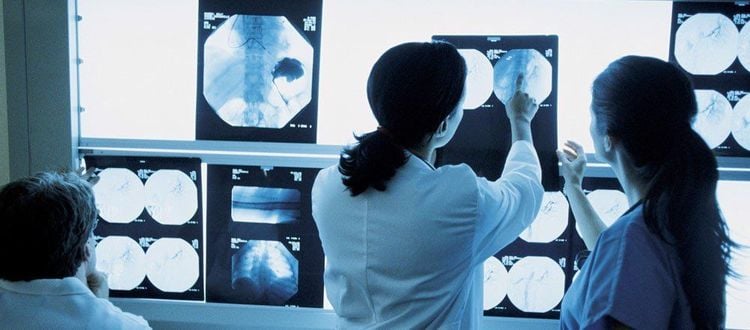

AI ngày càng được ứng dụng rộng rãi trong lĩnh vực y tế. AI ngày càng được ứng dụng rộng rãi trong lĩnh vực y tế. |

Hiện tại AI đã được sử dụng phổ biến trong chẩn đoán hình ảnh. Ảnh Vinmec.vn Hiện tại AI đã được sử dụng phổ biến trong chẩn đoán hình ảnh. Ảnh Vinmec.vn |